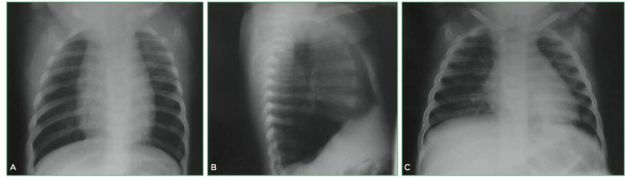

RX tórax achados

condensação, similar a quadros de pneumonias causadas por bactérias comuns; porém, associada a linfonodomegalias hilares ou subcarinais